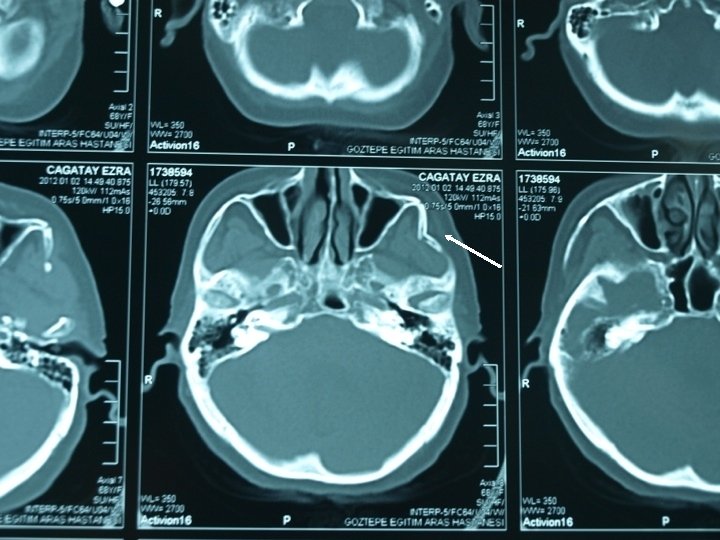

Orbital Floor (Blow-out) Fracture • Clinical findings – Periorbital hemorrhage- ecchymosis and subconjunctival hemorrhage – İnfraorbital nerve damage- paresthesia, anesthesia – Diplopia – Enophtalmos – Positive Forced duction test (+) – CT scan confirmation of fracture and herniation of orbital contents into maxillary sinus

Maxillary Fractures Le Fort Le. Fort I fracture is a horizontal maxillary fracture across the inferior aspect of the maxilla and separates the alveolar process containing the maxillary teeth and hard palate from the rest of the maxilla. Le. Fort II fracture is a pyramidal fracture starting at the nasal bone and extending through the ethmoid and lacrimal bones; downward through the zygomaticomaxillary suture; continuing posteriorly and laterally through the maxilla, below the zygoma; and into the pterygoid plates. Le. Fort III fracture or craniofacial dysjunction is a separation of all of the facial bones from the cranial base with simultaneous fracture of the zygoma, maxilla, and nasal bones.

Maxillary Fractures – Periorbital hemorrhage – Nasopharengeal hemorrhage – facial edema – intaoral lacerations – Maloclussion – Facial elongation – Maxillary retrution – Anterior open bite – Maxillary dental arch mobility – Rhinorrhea (Le Fort II ve III % 250